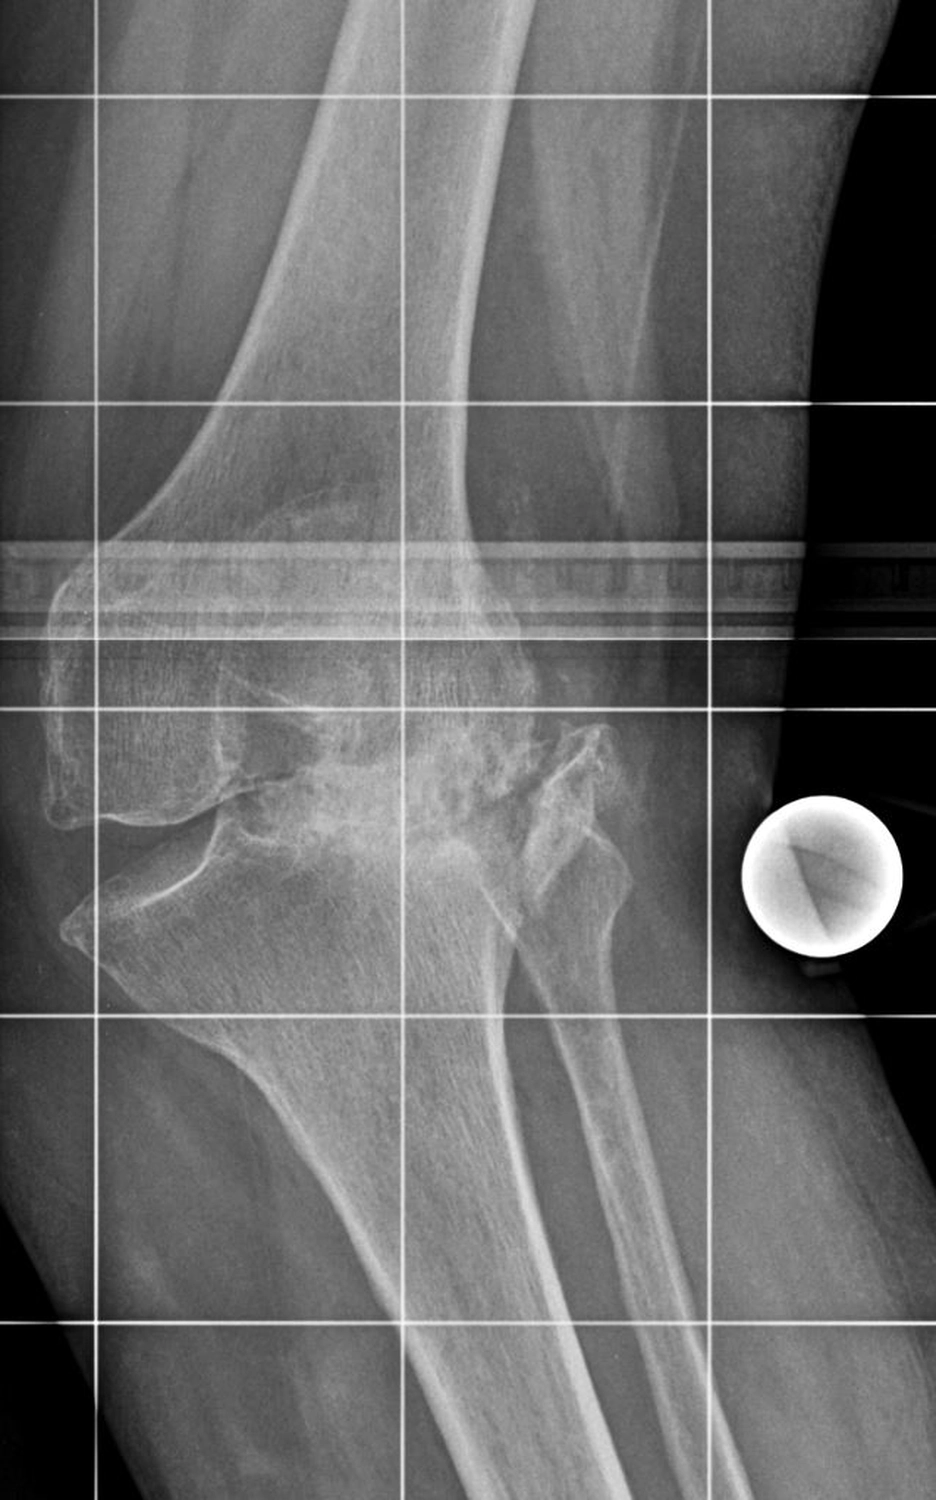

Das Kniegelenk ist das größte und eines der am stärksten belasteten Gelenke des menschlichen Körpers. Bei jeder Bewegung – Gehen, Treppensteigen, Hocken oder Stehen – wirken erhebliche Kräfte auf die Gelenkflächen von Oberschenkelknochen (Femur), Schienbein (Tibia) und Kniescheibe (Patella).

Diese Flächen sind von einer glatten Knorpelschicht überzogen, die wie ein Stoßdämpfer wirkt und ein reibungsloses Gleiten ermöglicht. Im Verlauf des Lebens kann sich dieser Knorpel jedoch abnutzen oder geschädigt werden – man spricht dann von einer Arthrose.

Die Kniegelenksarthrose (Gonarthrose) kann viele Ursachen haben. Häufig sind mehrere Faktoren beteiligt, die sich gegenseitig verstärken.